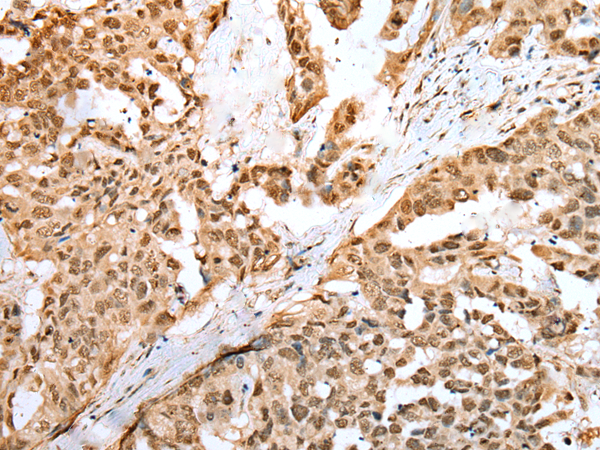

IHC positive control: |

Human breast cancer and human thyroid cancer |

IHC Recommend dilution: |

25-100 |